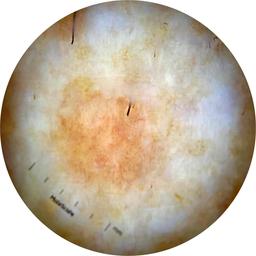

ISIC_6708537

Information

2077 x 2077

Clinical

Field Value

acquisition_day 525

age_approx 70

anatom_site_1 Upper extremity

anatom_site_general upper extremity

concomitant_biopsy False

diagnosis_1 Benign

diagnosis_confirm_type single image expert consensus

family_hx_mm False

fitzpatrick_skin_type I

image_manipulation instrument only

image_type dermoscopic

lesion_id IL_6558300

patient_id IP_3297880

personal_hx_mm True

sex female